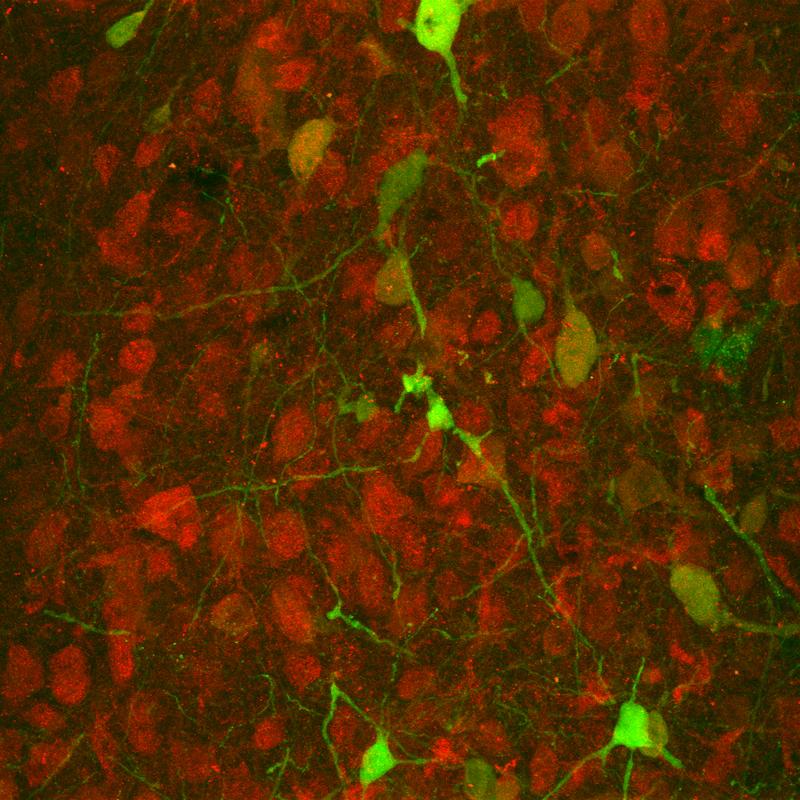

Mit genetischen Methoden koppelten die Bochumer Forscher Sehpigmente, die im Auge von Maus und Mensch vorkommen, an die Signalwege der Serotoninrezeptoren. Mit blauem Licht oder rotem Licht konnten sie so den Signalweg des 5-HT1A Rezeptors gezielt anschalten. Diese Methode der Optogenetik treibt Stefan Herlitze bereits seit 2005 voran und ist damit Vorreiter auf diesem Gebiet. Die lichtaktivierbaren Serotoninrezeptoren lassen sich auf wenige Millisekunden genau anschalten, sind im Vergleich zu bisherigen optogenetischen Werkzeugen extrem lichtsensitiv und lassen sich immer wieder aktivieren. „Wir hoffen, dass man in Zukunft mithilfe dieser optogenetischen Tools besser verstehen kann, wie Angst und Depressionen entstehen“, resümiert RUB-Neurowissenschaftlerin Dr. Olivia Masseck.

Die Forscher zeigten auch, dass sie über die lichtaktivierbaren Rezeptoren das Verhalten von Mäusen modifizieren können. Schalteten sie per Licht das Serotoninrezeptorsignal in einem bestimmten Hirnbereich an, waren die Mäuse im Verhaltenstest weniger ängstlich.